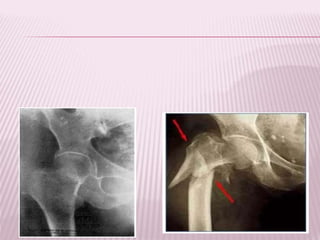

FRACTURA CAPITAL

 Aquellas comprendidas en la zona articular

de la cabeza femoral.

Se produce por

mecanismos de

trauma de baja

energía

Tipo I: Fractura por debajo del

ligamento redondo.

Tipo II: Fractura por encima del

Compromiso de zona de apoyo

Tipo III: I y II con fractura del

cuello femoral.

Tipo IV: cualquiera de las

anteriores mas fractura del

acetábulo,

Clasificación de

Pipkin